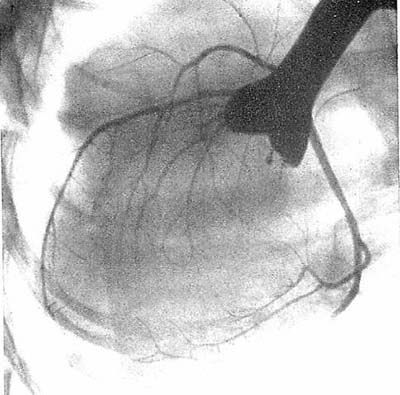

図7. 右頸静脈から太いゴム製カテーテルを右房に挿入し,心腔造影に成功した.右心系,肺動脈がよく造影されている.正常例.

【要旨・解説】頸静脈をカットダウンしてゴム製カテーテルを右房あるいは右室内に挿入し,初めて臨床的に有用な心腔造影に成功した報告である.造影剤は70% Diodrast 50~90ccを使用している.原則として造影剤注入終了時に撮影しているが,必要に応じて適当な間隔をおいて時相をおいて複数回撮影している.撮影方向は原則として正面,側面像である.造影剤注入法については記載がないが,0.75~1秒で注入すると書かれており,これは現在から見てもかなりの注入速度である.カテーテル径も不明だが,写真にうつっているカテーテルはかなり太く,おそらく機械式インジェクターを使用したのであろう.

1927年にMonizも頸静脈からカテーテルを挿入して心腔造影を試みているが,造影剤がヨウ化ナトリウムであったため,十分な濃度が得られず,臨床的に有用な画像はえられなかった.1937年にCastellanosが小児の右心系,1939年にはRobbが成人の両心系の造影に成功しているが,いずれも肘静脈からの造影剤注入であったため,造影剤が稀釈され,特に成人では十分な造影が得られなかった.本論文は心腔内に太いカテーテルを挿入して,大量の造影剤を急速注入することにより臨床検査としての心血管造影の端緒となった.1929年に心腔内カテーテル挿入に成功したForssmannは,その本来の目的である心腔造影には失敗したが,その悲願がここにきて初めて成就したとも言える.

正常像,リウマチ性心疾患,先天性心疾患などが供覧されているが,いずれも十分診断に耐える画質である(図7).単純X線写真の心弓と心腔の関係,巨大左房による二重輪郭など基本的な解剖学的事項に加え,リウマチ性弁膜症,総動脈幹遺残などの複雑心奇形にも言及している.